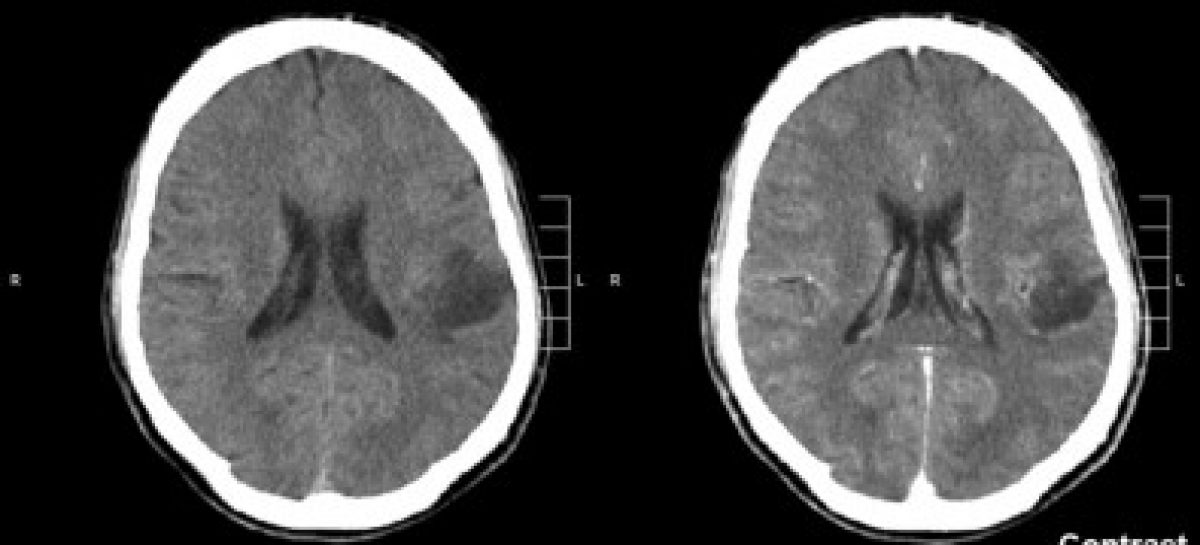

A fim de tentar encontrar essa resposta, os pesquisadores analisaram quatro linhagens diferentes de células de glioma sensíveis e resistentes à temozolomida (TMZ) – quimioterápico que é a principal opção de fármaco disponível hoje para o tratamento de glioma, também usado para combater melanoma ao induzir danos no DNA e aumentar os níveis de estresse oxidativo das células tumorais.